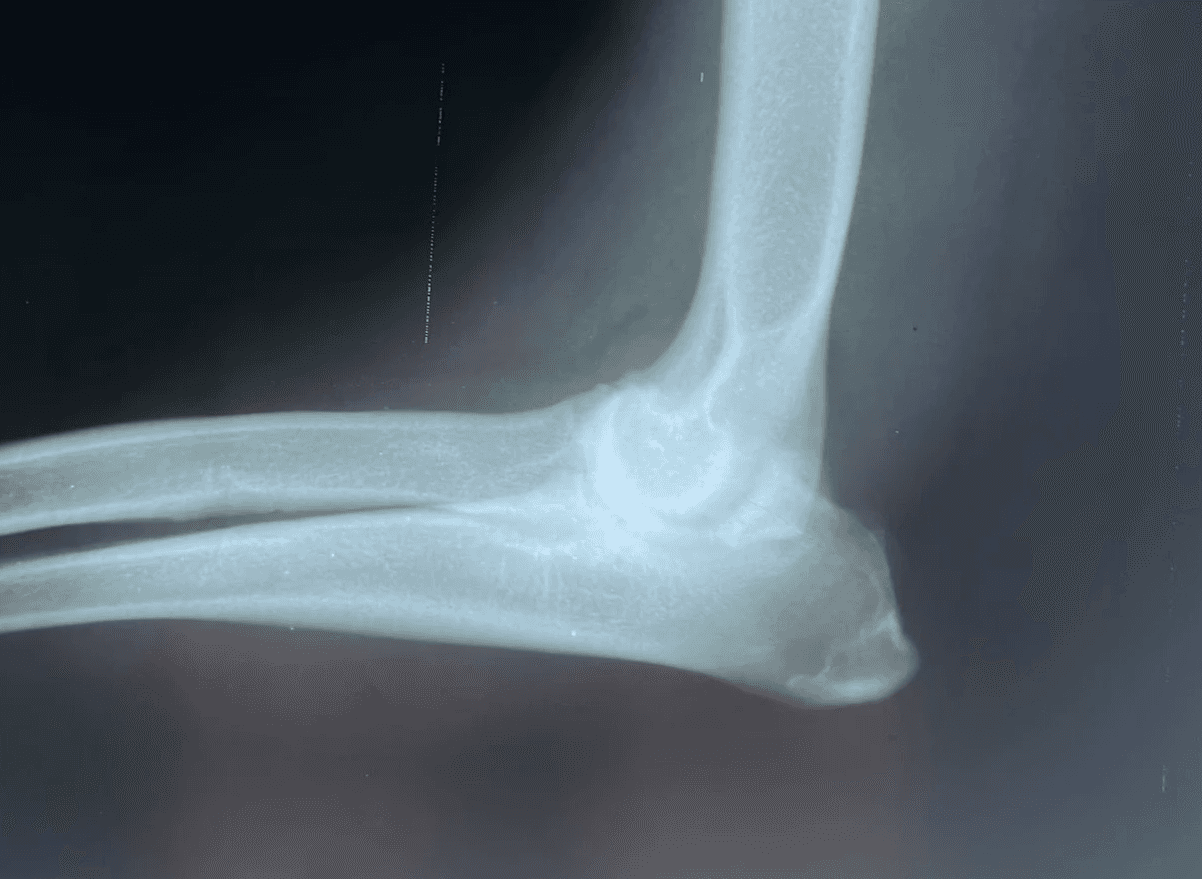

X-rays of the injured area are required to confirm the fracture and determine the best treatment approach. At least two straight views (lateral and cranial/caudal) are necessary for all fractures because a single view can disguise or miss the problem. Pain relief and sedation medications are often needed to obtain accurate X-ray images comfortably and safely.

Elbow Luxation with chip fracture missed on single view